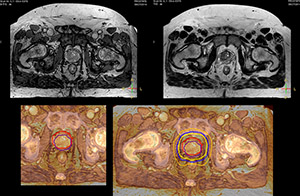

Beaumont Health System (Royal Oak, Michigan, USA) is one of the largest health systems in the USA, with eight hospitals and 153 outpatient sites, a medical school and a research institute. The Radiation Oncology (RO) department houses a dedicated Ingenia MR-RT solution that is routinely used for clinical and research MR-RT activities. “The main reason to integrate MR imaging in RT planning is the superb soft tissue contrast that allows detailed delineation of tumors and healthy organs, which is crucial for RT planning,” says Craig W. Stevens MD, PhD. “MR also provides information on functional and biological activities in tumors, background tissue and normal organs, which may also be used in RT planning,” says physicist Di Yan, DSc, FAAPM.” “We currently use MR-RT mainly in the abdomen and pelvis region: prostate, colorectal, pancreatic, cervical, and liver. Also in the brain, we are starting to use it,” says Dr. Yan.

“The biggest problem for CT-based planning, especially in prostate, is you can’t see the cancer very well,” says Dr. Stevens. “On CT it can be quite challenging to see the edge of the prostate especially at the apex. When the edge of the prostate can’t be delineated well on CT, radiation oncologists will increase their margins a little bit so they don’t miss it, but that can also increase toxicity.” “Using MR, the prostate is well delineated. We quickly see the edges of cancerous tumors like in prostate cancer, and as normal structures can be defined, we can optimize the treatment plan to protect these organs and their normal function. This can potentially improve the outcome. And it improves workflow as well. We can contour more quickly, confident that the tumor is going to be in the field.” “The Ingenia 3.0T MR scanner provides high resolution allowing us to make scans fast for the patients. It also gives the potential to include methods like MR spectroscopy and diffusion weighted Imaging, which we’re in the process of doing right now,” Dr. Stevens adds.

“When a patient registers, first CT simulation and MR simulation are done, followed by CT-MR registration on Pinnacle3. Then the target and normal organ delineation is performed on MR images. Meanwhile we create a reference CT image for online treatment and localization correction. During the treatment phase we can perform additional MRI scans to visualize the anatomy changes and create an adaptive plan. This plan basically adapts the treatment plan to the changes.” “Along with its great benefits, MR has introduced some new challenges,” Dr. Stevens says. “Radiation therapy teams generally have no experience with MR. The Philips training helped us to implement fully the things we can do with the Ingenia MR-RT system. So the training, as well as having a good MR physicist, is critical.”